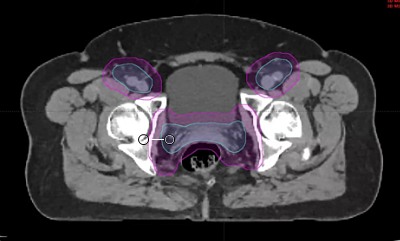

endometrial adenocarcinoma, para-aortic nodes, PET CT, diabetes, charcot arthropathy, groin nodes, pelvis, negative cervical margins, cisplatin, small bowel, Harkenrider, contouring, MRI, tumor, vaginal bleeding, relapse, persistence, cylinder, dose distribution, dosimetry, brachytherapy, fractio...

squamous cell carcinoma, dysplasia, PET, SIB, brachytherapy, endocervical, MRI, nodal location, inguinofemoral, right external iliac, CTV, deescalation, dosimetry, sigmoid, hysterectomy, concurrent chemoradiation, stenotic cervix, abdominal infection, external planning, avoid structure, antibioti...

chemotherapy, radiation therapy, sandwich regimen, brachytherapy, well differentiated endometrioid adenocarcinoma, neoadjuvant chemotherapy, small bowel, dilation, dosimetry, gross disease dose, MRI, cirrhosis, external beam radiation, Rotte Y applicator, CT scan, dual tandem, 3-D printing, endom...